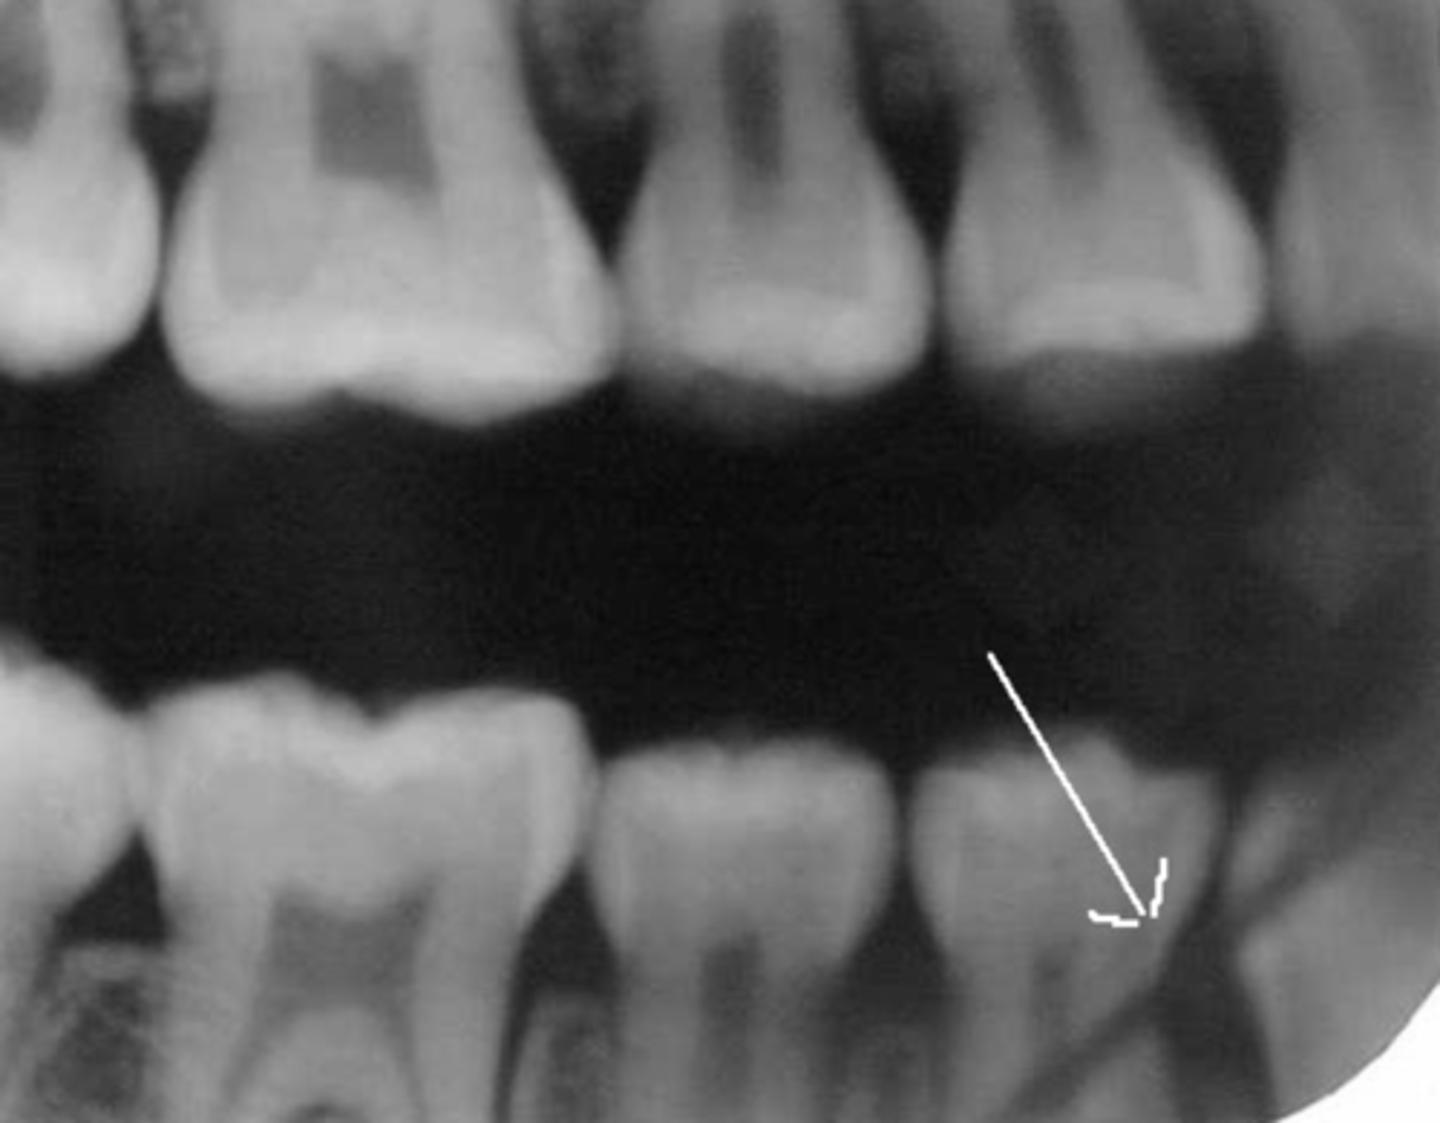

Incorrect Horizontal Angulation

-Overlapped contacts

-CR was not directed through the interproximal spaces, resulting in the proximal surfaces of adjacent teeth appear overlapped in the PA.

-Occurs in both paralleling and bisecting technique

-To prevent direct the x-ray beam through the interproximal regions

Incorrect Horizontal Angulation -->Bite-Wing

-CR was not directed through the interproximal spaces.

Tube Head & PID-->Overlapped teeth Contact

Cause - misdirecting the beam through the contacts, the x-ray beam/PID not perpendicular to the image receptor, Not positioning the image receptor parallel to the teeth

Correction - Move either mesial or distal depending on the mistake.

"Move toward it to fix it"

Mesiodistal overlap

-The x-ray beam is directed obliquely from mesial to distal

Cause - If overlapping is more severe in the posterior region, cone is angled too much form the mesial.

Correction - Shift the PID toward the posterior or direct the CR more from the distal

Distomesial overlap

-The x-ray beam is directed obliquely from distal to mesial

Cause - If overlapping is more in the anterior region, cone is angled too much from the distal

Correction - Shift the PID toward the anterior, direct the central ray beam more from the mesail